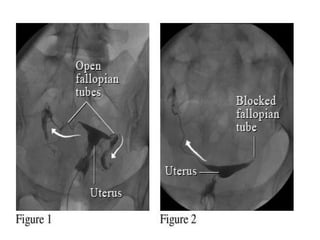

• Tubal occlusion. (a)

fallopian tube

• ampullary portionof the left fallopian tube, a finding that is consistent with a hydrosalpinx. No contrast material spillage is seen on the left side. The right fallopian tube is abruptly cut off

• Tubal occlusion.(a) Spot radiograph demonstrates abrupt cutoff of the left fallopian tube